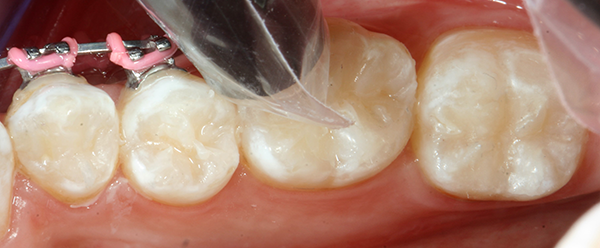

Using the Ball-Point Applicators, I applied a generous amount of OptiBond All-In-One adhesive to the enamel/dentin surface. I scrubbed the surface with a brushing motion for 20 seconds, and then applied a second application of OptiBond All-In-One adhesive with a brushing motion for 20 seconds. I then dried the adhesive with gentle air first and then medium air for five seconds with oil-free air, and then light cured for 10 seconds with the Kerr Demi™ Plus Curing Light (Fig. 3).

Fig. 3 Fig. 4